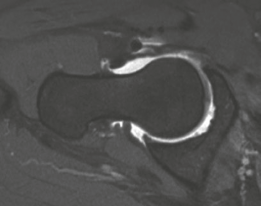

From an osseous perspective, the normal adult hip relies on a delicate balance of version and coverage. The acetabulum is typically anteverted approximately 15° to 20°, with a normal LCEA between 25° and 39°, and a roof inclination angle approaching zero. The proximal femur normally exhibits 10° to 15° of anteversion. In our complex instability cohort, this relationship is severely distorted. A patient may present with an LCEA of 18° (frank dysplasia) and a roof inclination of 20° (a steep, up-sloping sourcil), leading to a severely diminished weight-bearing surface area. When this is compounded by high femoral anteversion—such as 36° measured on MRI—the femoral head is driven anteriorly. This creates a functional anterior uncoverage that is exponentially worse than the radiographic coronal measurements imply.

Advanced imaging is non-negotiable in the revision setting. A high-resolution MRI or MR arthrogram of the hip is required to assess the articular cartilage, the integrity of the ligamentum teres, and the state of the remaining labrum or capsular scar tissue. Anterolateral loss of joint cartilage is a frequent finding in dysplastic hips post-labral resection. Furthermore, a CT scan or MRI utilizing torsional sequences from the hip through the knee is essential to quantify femoral version. A measured femoral anteversion of 36° dictates that a derotational femoral osteotomy (DFO) must be incorporated into the surgical plan to restore normal biomechanics and prevent recurrent anterior subluxation post-operatively.